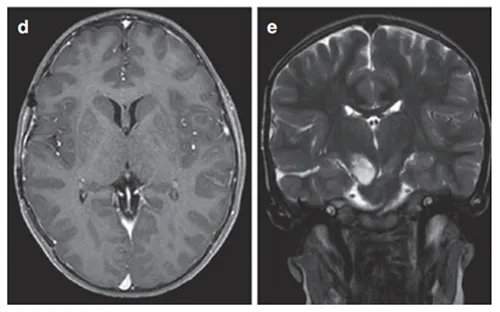

MRI显示右侧丘脑存在环形强化结节状肿瘤,累及内侧颞叶结构。

Rutka教授实施经颞中回-脑室入路次全切除术,病理证实为WHO I级毛细胞星形细胞瘤,BRAF重复融合、BRAF V600E及H3K27M检测均为阴性,基因检测检出NF1基因变异。

术后影像学随访显示丘脑部分切除及中脑残留病灶,遂制定个体化辅助放疗方案,患儿治疗反应良好。术后6个月复查确认肿瘤控制情况稳定。